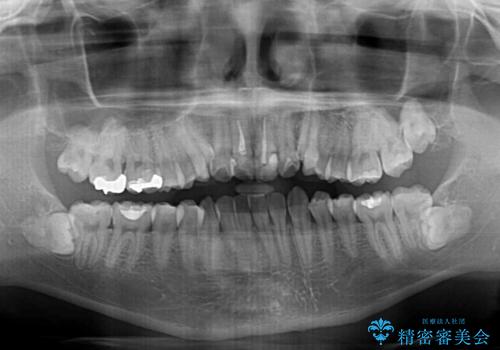

上下ともに八重歯が顕著であったため、上下左右の第一小臼歯4本を抜歯し、ワイヤー装置での抜歯矯正を行うこととしました。

前歯は根管治療が必要な歯を事前に根管治療を行い、矯正治療後にオールセラミッククラウンにて補綴治療を行うこととしました。